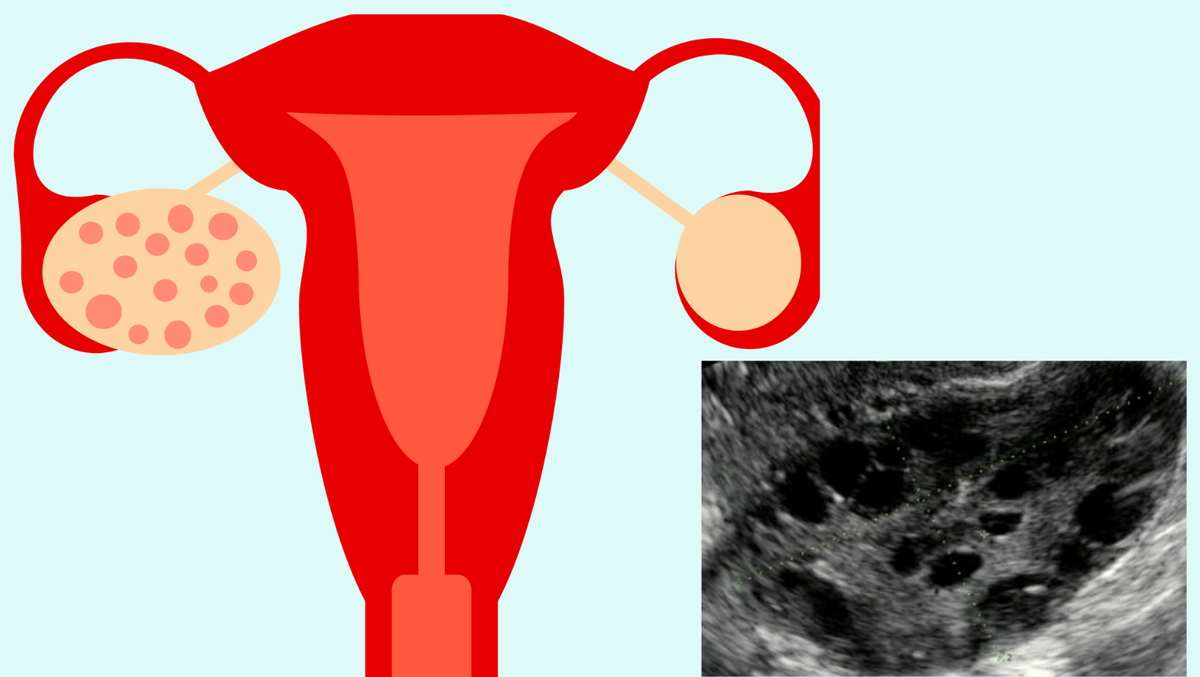

Мультифолликулярные яичники

Мультфиолликулярные яичники – это не диагноз. Это всего лишь ультразвуковое заключение, которое может означать наличие заболевания, а может ни о чем не говорить и быть случайной находкой.

Когда можно говорить о наличии мультифолликулярных яичниках?

Если в структуре яичника определяется 12 и более (по критериям некоторых медицинских сообществ 20 и более) мелких фолликулов диаметром до 9 мм и/или объем яичника составляет 10 и более мл. Чтоб посчитать объем яичника нужно перемножить его ширину, длину и толщину, и полученную цифру разделить пополам.

Мультифолликулярные яичники могут быть случайной находкой, и у женщин не имеющих проблем с регулярностью менструаций, избытком андрогенов и трудностей с зачатием ни о чем не говорят и не требуют лечения.

Синдром поликистозных яичников (СПКЯ) – это заболевание, одним из критериев которого как раз и будут являться мультифолликулярные яичники, выявленные при ультразвуковом исследовании. Но для постановки диагноза необходимы и другие симптомы, одного УЗИ заключения недостаточно.